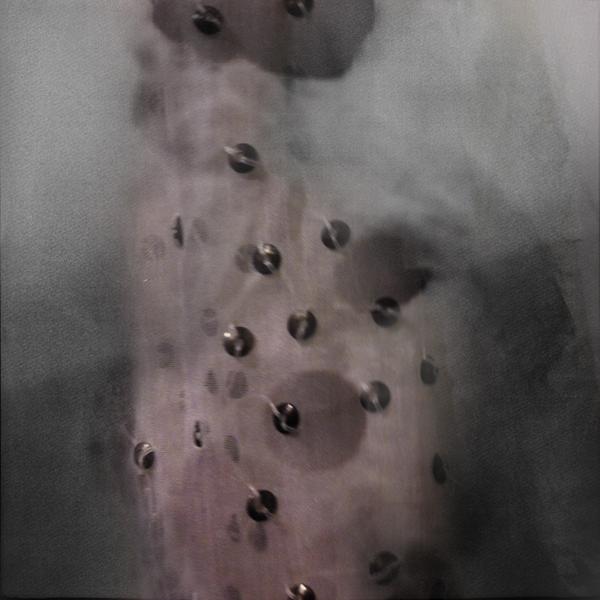

Within these photographs, medical imagery digitally combined with images of fabrics reveal hauntingly ethereal portraits of people when they are their most vulnerable. Alterwitz exposes these emotions with stark bluntness and at other times with tenderness. While the details of the skin and features are blurred, lost in the medical scan, expression can be seen in the tilt of a head, the rise of a chin, the lean of a shoulder. Combined with the layering of fabric images, the result is an eerie enshrouding of faces and figures that addresses notions of loss and remembrance, enlightenment and anger, and life and death. The fabrics, which are typically used to clothe our bodies, are stripped away and blended with the images of our internal organs and structures revealing beauty as it reflects life, contemporary culture, and the intense realities of everyday life, shedding light on the struggles and fears related to being human.